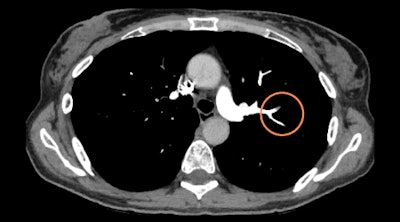

Israeli artificial intelligence (AI) software developer Aidoc's pulmonary embolism detection algorithm is designed to identify blood flow obstructions on pulmonary CT angiograms and flag critical exams for urgent review by radiologists.

Analyzing images right after they are acquired, the deep learning-based software can assist in managing pulmonary embolism cases without disrupting workflows and enable radiologists to quickly attend to time-sensitive and potentially life-threatening cases, according to the vendor. Researchers at the University Hospital of Basel in Switzerland highlighted the benefits of the software in a presentation at ECR 2019 in Vienna.